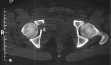

Radiographs:

Radiographs revealed a vertical buckle fracture of the right inferior sacrum, oblique fractures of the superior and inferior rami on the right and a fracture through the medial acetabulum. Obturator and iliac oblique inlet and outlet pelvic views, and a thin cut CT with 3-D reconstruction of the acetabulum were performed. These elucidated a comminuted anterior wall with fracture line extending to the posterior column. The posterior column was non-displaced. The pelvic fracture was non-displaced.

COMPUTED TOMOGRAPHY: R/O intra-articular loose fragments, Plan for surgery.